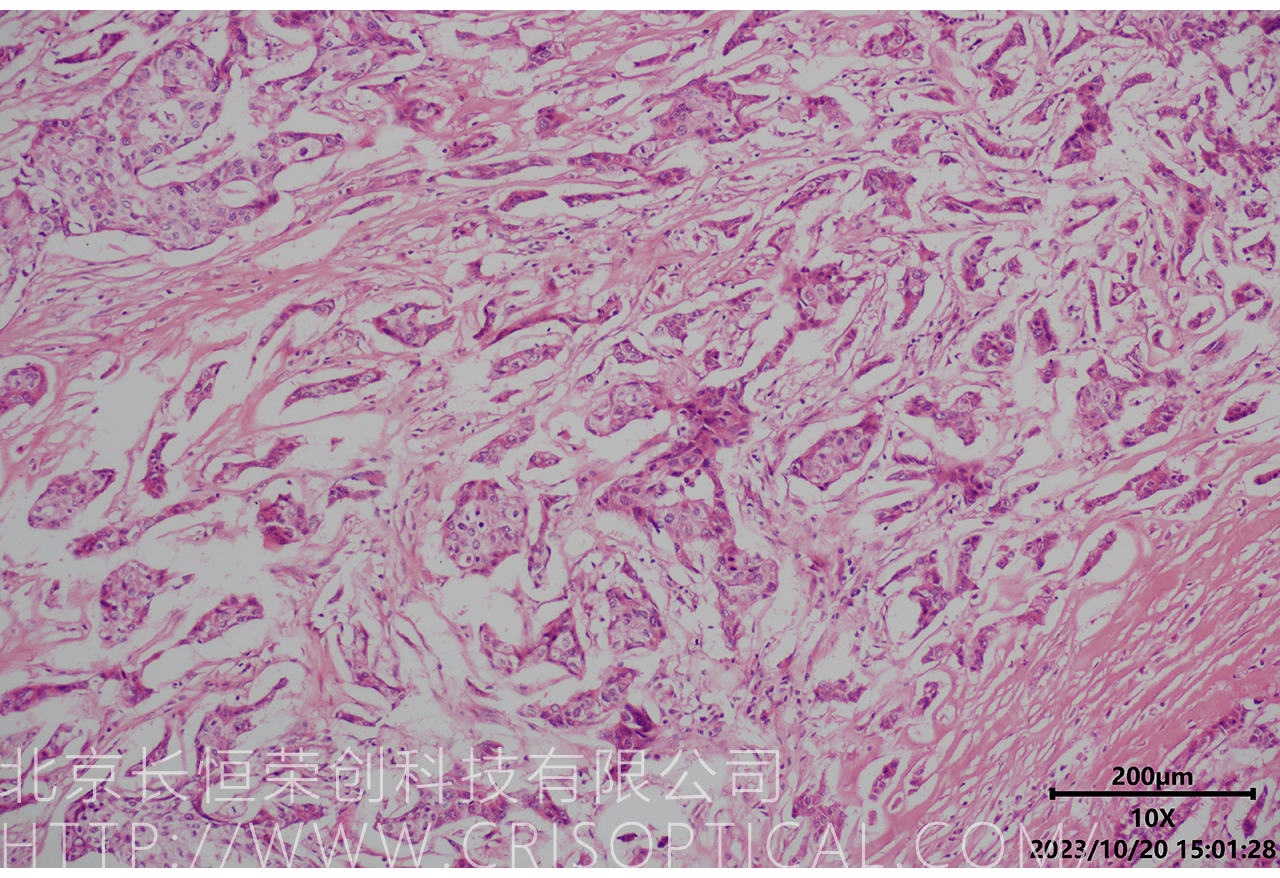

腫瘤診斷:對(duì)癌癥和其他腫瘤的病理切片觀察是確定腫瘤類型、分級(jí)和分期的關(guān)鍵步驟。醫(yī)生通過觀察組織樣本中的細(xì)胞形態(tài)、核形狀、分裂活性和其他特征,可以識(shí)別腫瘤的類型,幫助決定治療方法。